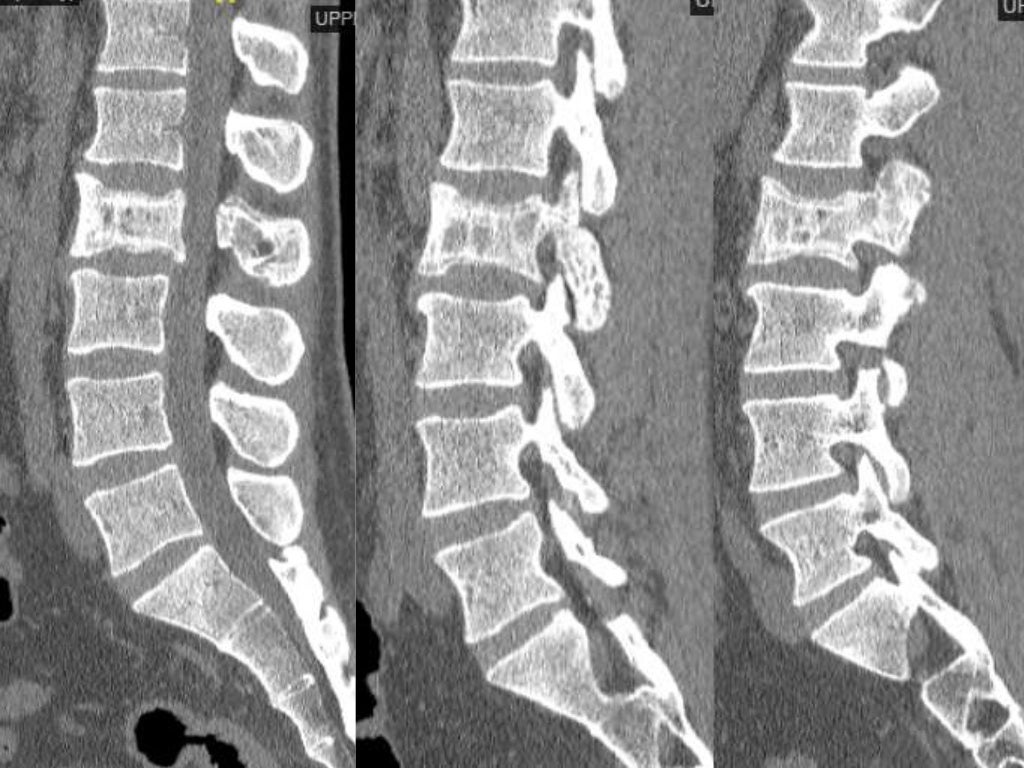

From www.ctisus.com

Paget's Disease of the Lumbar Spine on Xray X Rays Case Studies CTisus CT Scanning Paget's Disease Lumbar Spine Icd 10 Code The disease can lead to. Paget's disease of bone causes your bones to grow larger and weaker than normal. They also might break easily. M51.36 is a new code for other intervertebral disc degeneration, lumbar region, effective from 2024. Learn about the epidemiology, pathophysiology, diagnosis, and treatment of paget disease of bone, a benign skeletal disorder. Paget's disease is an. Paget's Disease Lumbar Spine Icd 10 Code.